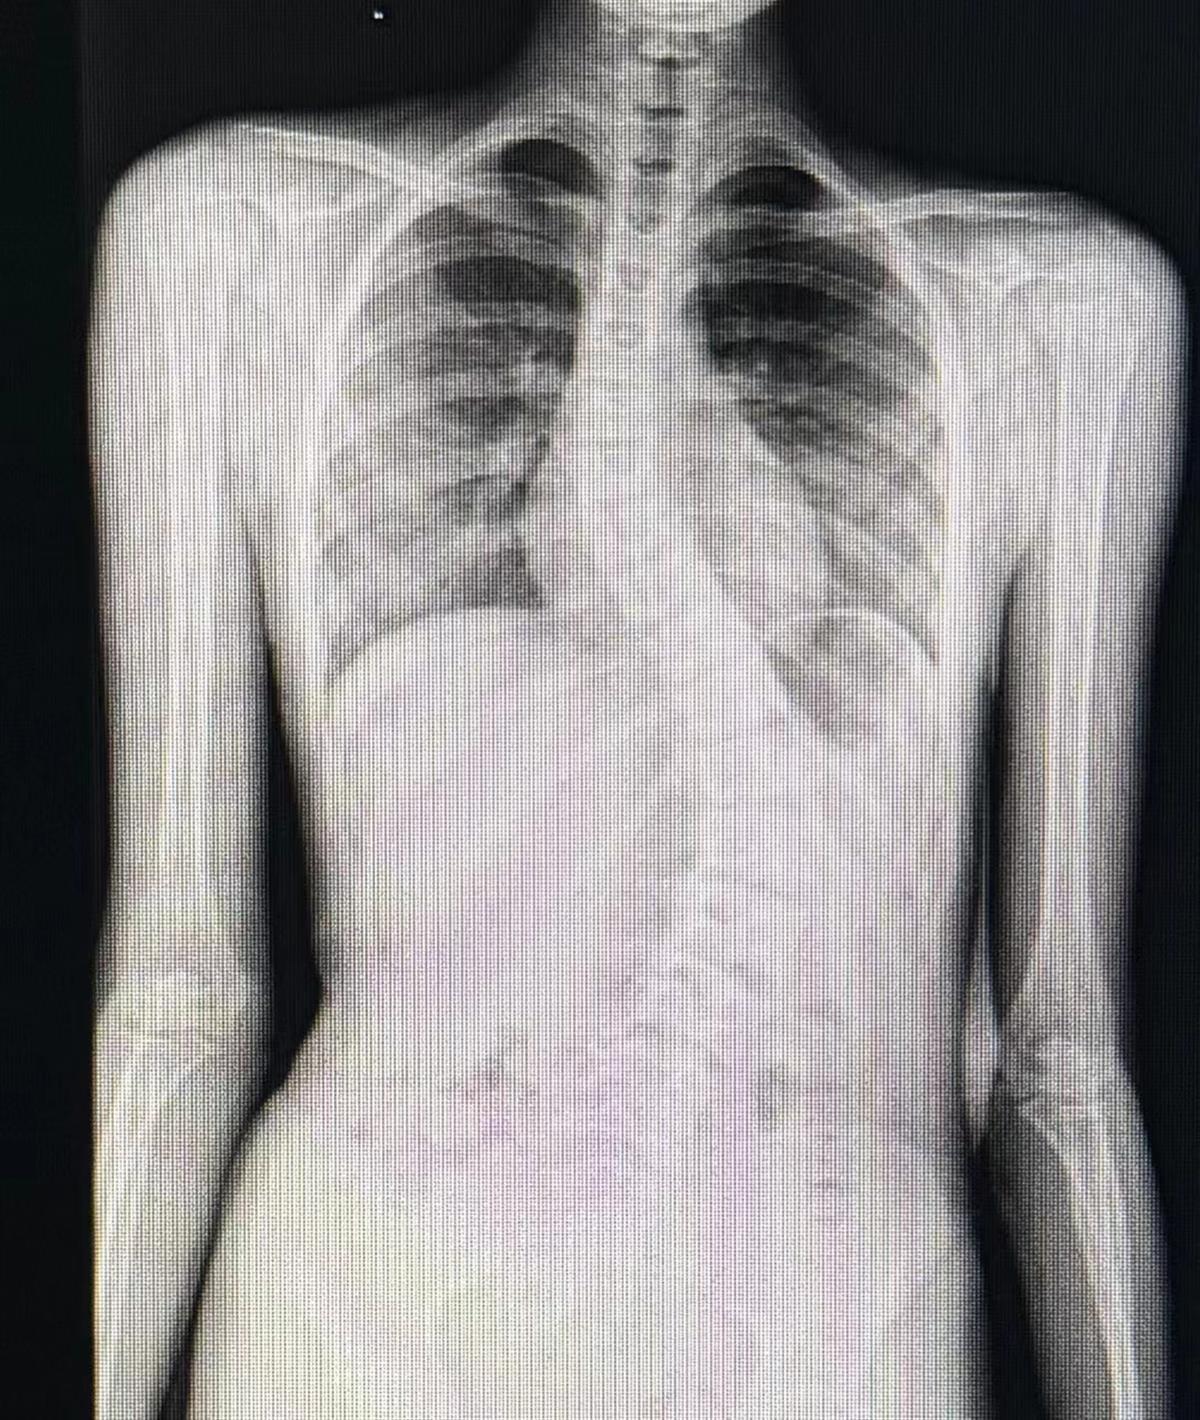

珍珍术前的脊柱影像图

李凡对珍珍进行了查体,发现她后背及腰部明显双侧不对称,肩膀左低右高,进行脊柱全长X片检查后,诊断为青少年特发性脊柱侧弯。“珍珍的脊柱侧弯角度已经达到了64度,腰背部弯曲畸形十分明显,所以孩子会出现坐不正、双肩不等高的情况。”李凡介绍,由于珍珍的脊柱弯曲角度太大,需要手术矫正,否则畸形还会进一步加重,并引起腰背部疼痛,影响今后的学习与生活。